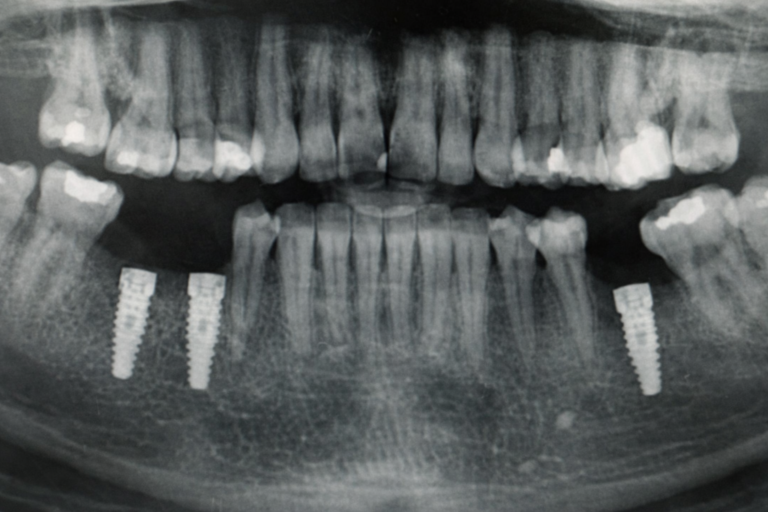

Consta de unos pernos metálicos hechos en titanio, que parecen tornillos y se ubican en el hueso de la mandíbula con el cual se solucionará la ausencia de dientes.

- Implantes Convencionales: son los implantes más usados. Tienen una forma pequeña de tornillos, hechos de titanio y se colocan en el hueso alveolar de la mandíbula o el maxilar para producir la fase de osteointegración.

- Estudios: tomografía, radiografía panorámica, análisis de laboratorio en caso de requerir.

- Tomografía o radiografía final para revisión de fase previa. Aquí lo que vamos a revisar es la recuperación, la cicatrización del hueso alrededor de los implantes, estabilidad del mismo, evaluar si hay infecciones que deban ser tratadas o controladas.